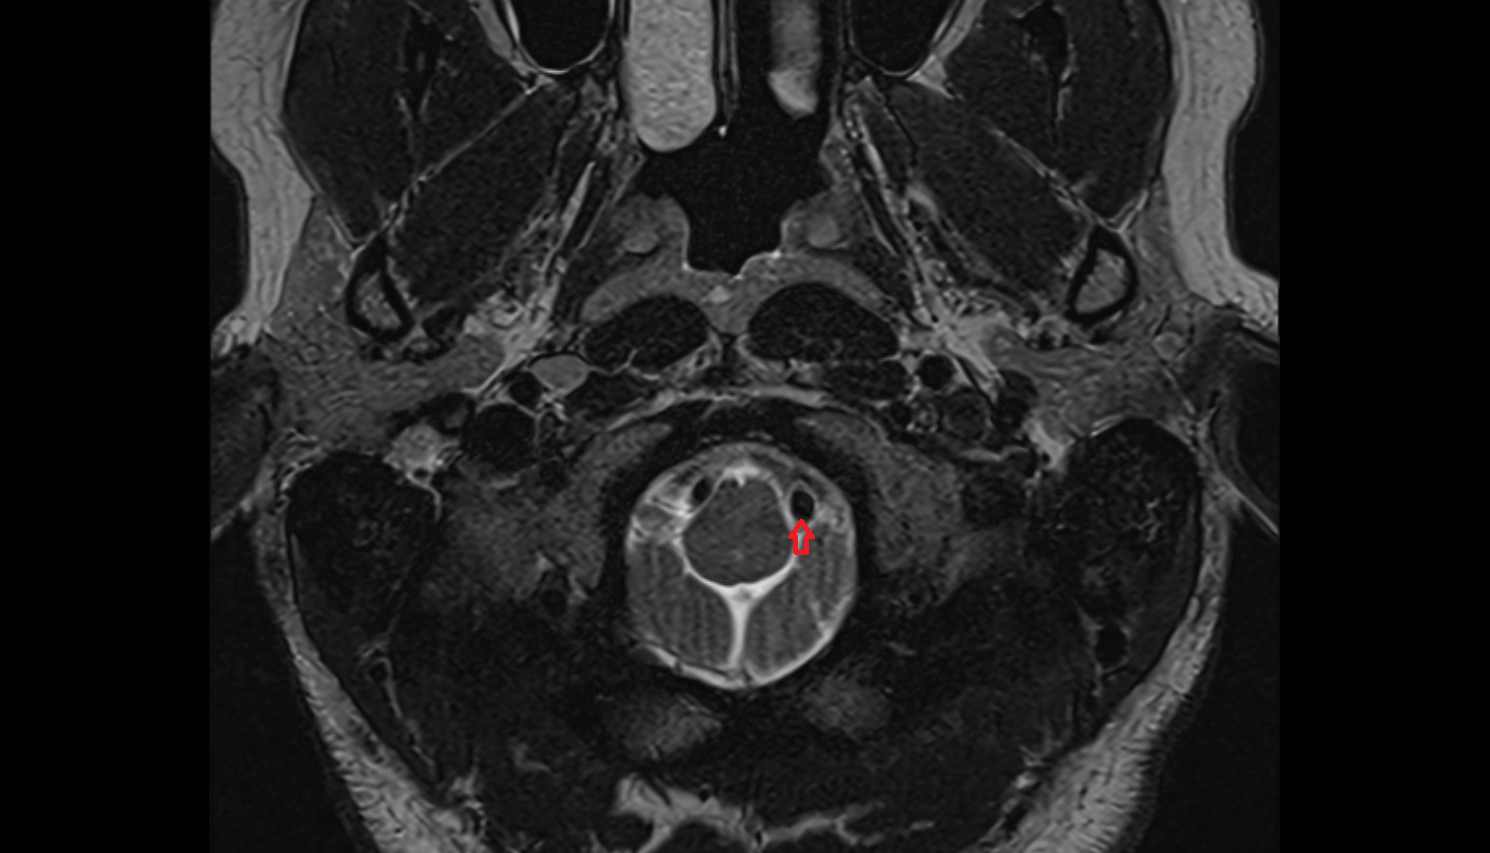

- Spinal cord

- subarachnoid space of spinal cord

- Premedullary cistern